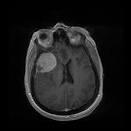

Meningioma patients diagnosed 2007–2009 and the association with use of mobile and cordless phones: a case–control study

Background: To study the association between use of wireless phones and meningioma.

Methods: We performed a case–control study on brain tumour cases of both genders aged 18–75 years and diagnosed during 2007–2009. One population-based control matched on gender and age was used to each case. Here we report on meningioma cases including all available controls. Exposures were assessed by a questionnaire. Unconditional logistic regression analysis was performed.

Results: In total 709 meningioma cases and 1,368 control subjects answered the questionnaire. Mobile phone use in total produced odds ratio (OR) = 1.0, 95% confidence interval (CI) = 0.7-1.4 and cordless phone use gave OR = 1.1, 95% CI = 0.8-1.5. The risk increased statistically significant per 100 h of cumulative use and highest OR was found in the fourth quartile (>2,376 hours) of cumulative use for all studied phone types. There was no statistically significant increased risk for ipsilateral mobile or cordless phone use, for meningioma in the temporal lobe or per year of latency. Tumour volume was not related to latency or cumulative use in hours of wireless phones.

Conclusions: No conclusive evidence of an association between use of mobile and cordless phones and meningioma was found. An indication of increased risk was seen in the group with highest cumulative use but was not supported by statistically significant increasing risk with latency. Results for even longer latency periods of wireless phone use than in this study are desirable.